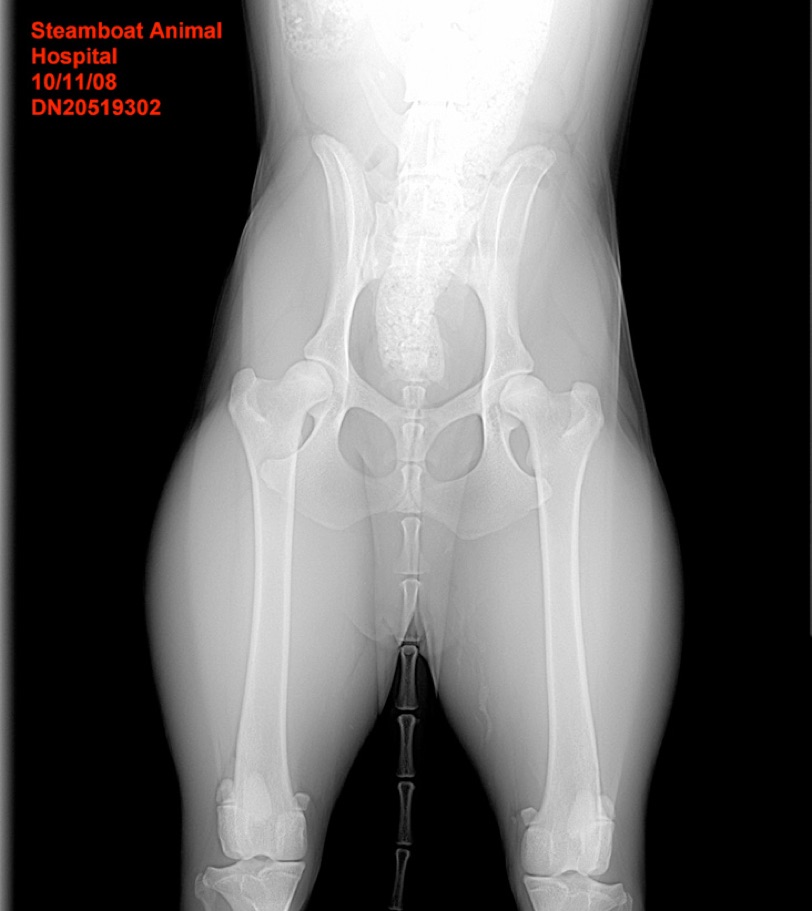

Swirl hip x-ray